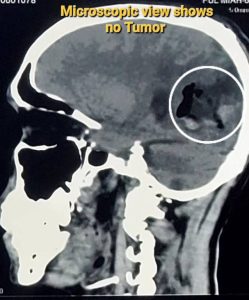

জিবিএম (Glioblastoma Multiforme - GBM)

GBM (Glioblastoma multiforme) হলো মস্তিষ্কের একটি অত্যন্ত আক্রমণাত্মক এবং দ্রুত বর্ধনশীল ক্যান্সার। এটি গ্রেড IV টিউমার হিসেবে শ্রেণীবদ্ধ, যা সবচেয়ে গুরুতর। GBM-এর চিকিৎসায় সার্জারি একটি গুরুত্বপূর্ণ ভূমিকা পালন করে, এরপর সাধারণত রেডিয়েশন থেরাপি এবং কেমোথেরাপি দেওয়া হয়।

GBM একটি আক্রমণাত্মক ক্যান্সার, তাই সম্পূর্ণরূপে টিউমার অপসারণ করা প্রায়শই সম্ভব হয় না কারণ এটি আশেপাশের সুস্থ মস্তিষ্কের টিস্যুতে ছড়িয়ে পড়ে। সার্জারির পরও কিছু ক্যান্সার কোষ অবশিষ্ট থাকে। এজন্য সার্জারির পর রেডিয়েশন এবং কেমোথেরাপির মতো অতিরিক্ত চিকিৎসার প্রয়োজন হয়।